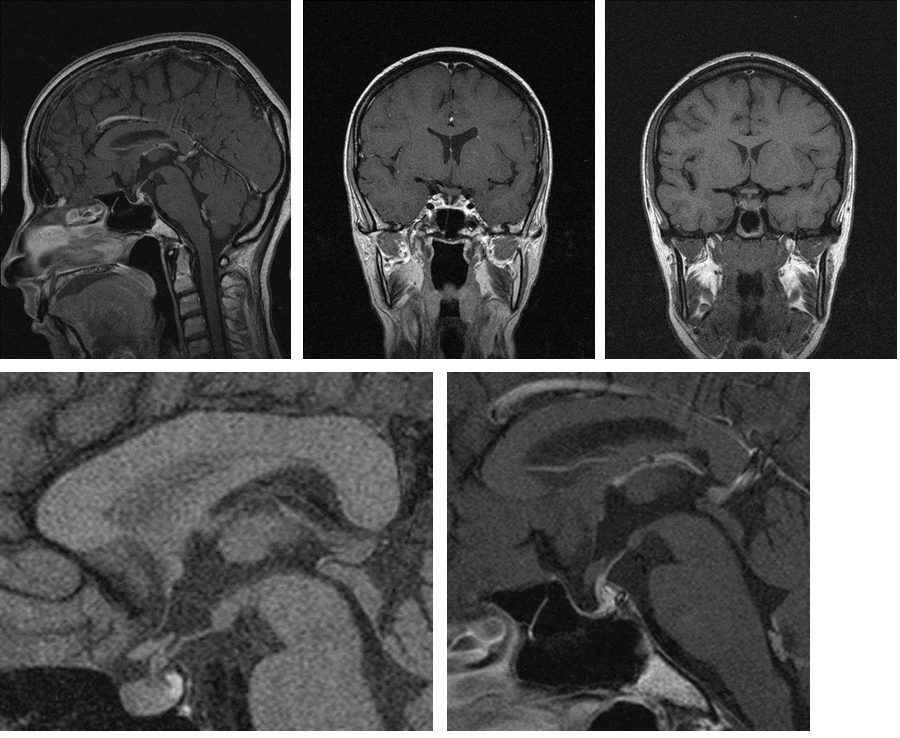

A magnetic resonance imaging (MRI) evaluation of the pituitary is the basic cornerstone of establishing a diagnosis. Generally, the presence of an empty sell in nearly 70% of patients while a partially empty is present in about 30%.in the acute stage, the image may show acute central infarction without bleeding in the hypertrophied gland. Over time subsequent imaging might demonstrate gland atrophy and partially or fully empty sella.10–12

Sheehan’s syndrome: Post-Partum Anterior Pituitary Necrosis (Figure 5) (Figure 6)

Imaging: MRI of pituitary gland